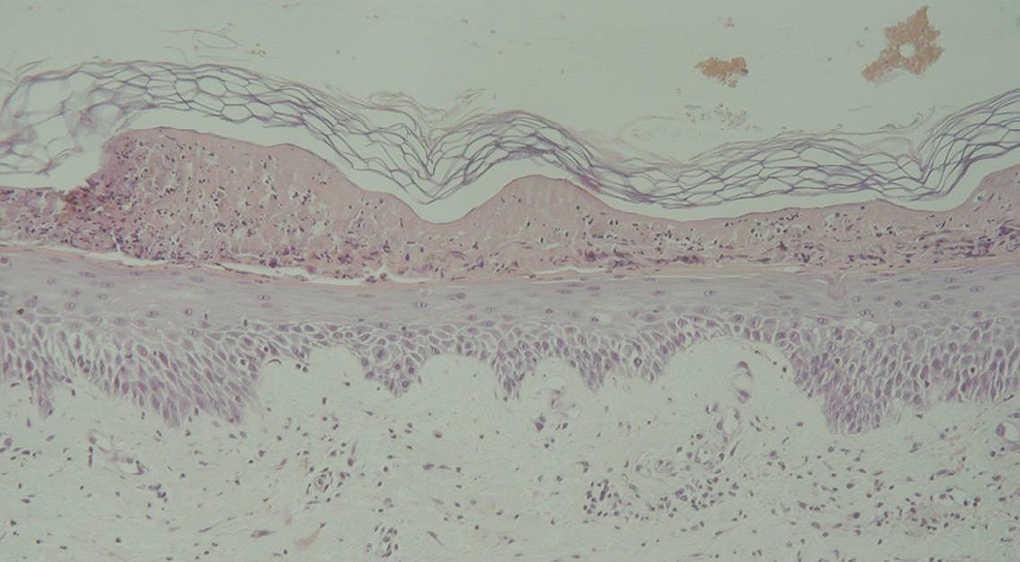

El hemograma, la bioquímica y el estudio de coagulación fueron normales. La biopsia cutánea mostraba una intensa necrosis en la mitad superior de la epidermis, con zonas de espongiosis en la zona inferior. En la dermis se encontraban infiltrados de linfocitos y neutrófilos, así como una moderada extravasación de hematíes (fig. 3). Asimismo, se observaba necrosis de glándulas sudoríparas ecrinas. No se apreciaron signos de vasculitis. Se pautaron corticoides orales, tópicos y antihistamínicos, y se resolvieron las lesiones cutáneas en aproximadamente 7 días.

Fig. 3.--Necrosis epidérmica e infiltrado linfohistiocitario perivascular en dermis. (Hematoxilina-eosina, x80.)